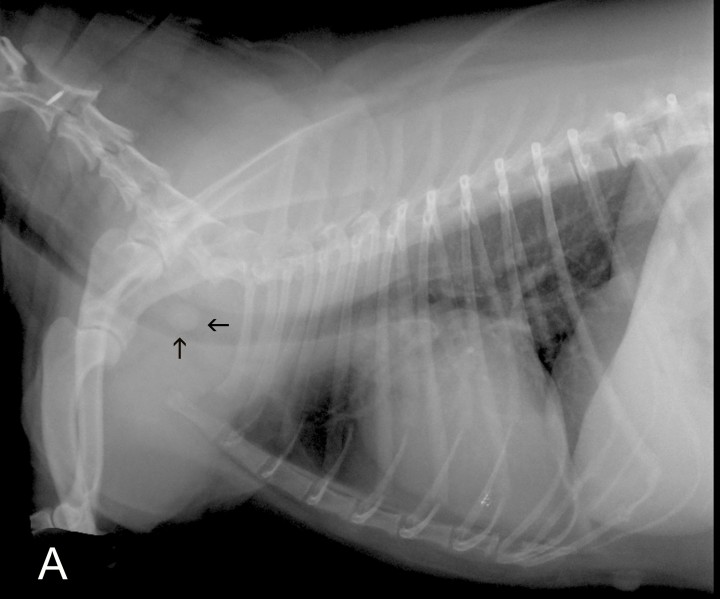

Figura 1

Radiografías de la cavidad torácica de una perra mestiza de 7 años. (A) Proyección lateral derecha. (B) Proyección ventrodorsal.

En la proyección lateral se visualiza una estructura de opacidad tejido blando y morfología redondeada en el interior de la luz traqueal en contacto con la pared dorsal de la tráquea, ocupando un 90 % de su diámetro, a nivel del cuerpo vertebral de C6. Tanto en la proyección lateral como en la ventrodorsal, el resto de la tráquea y la silueta cardiaca no presentan alteraciones evidentes y a nivel del parénquima pulmonar se aprecia un leve patrón bronquial (Fig. 2).

Figura 2

Radiografía de la cavidad torácica en proyección lateral derecha de una perra mestiza de 7 años, en la que se visualiza un leve patrón bronquial y una estructura redondeada de opacidad tejido blando en el interior de la tráquea (flechas), a nivel del cuerpo vertebral de C6.